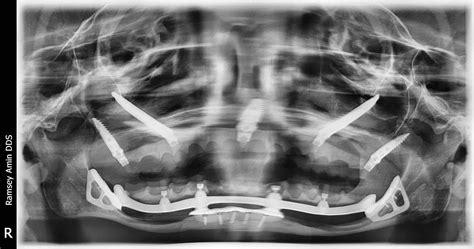

3. Dental Implants

Unlike bridges or dentures, dental implants serve as artificial tooth roots. By integrating with the bone, they provide the necessary physical stimulation that prevents further Dental Bone Loss, effectively preserving the jaw’s shape.

2. Bone Grafting

For patients who have already experienced significant loss, a bone graft is a common surgical procedure. Material is placed in the area of the bone loss to act as a scaffold for the body to grow new, healthy bone tissue.